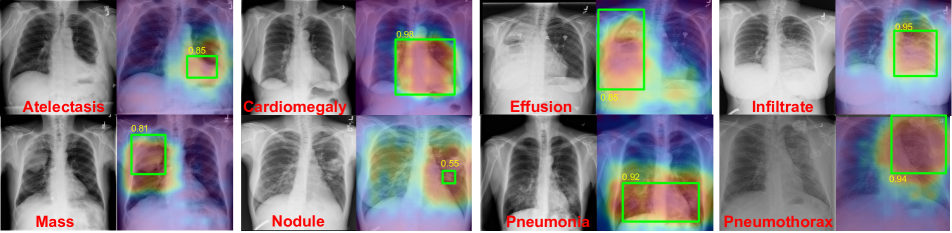

Refer to caption

Figure 5: Examples of localization results on 8 diseases along with ground truth bounding box annotations. In each pair, a chest radiograph (left) inputs into our model and the corresponding heatmap (right) is generated. The heatmaps produced from our model match with the ground-truth bounding boxes (green) annotated by radiologists and indicated good IoU results (yellow).

We generated our predicted bounding boxes by applying a naive thresholding (T=0.10.7𝑇0.1similar-to0.7T=0.1\sim 0.7) on the normalized heatmap with value ranged from 0 to 1 that obtained from our class-wise pooling layer. Examples are shown in Figure 5. No localization annotation was used during training process. The heatmaps were generated by our network with training only from image-level labels. All 880 images with bounding boxes ground truth were used for evaluation.

In Table 2, we compared our results with [8]. Our model achieved significantly higher IoU score over [8] on diseases with large lesion, such as ”Cardiomegaly” (abnormally large heart). The heatmap is well-fitted with the ground truth bounding box. Disease such as ”Infiltration” (substance such as blood infiltrates through vessel into lung) and ”Pneumonia” (inflammation in lung) that affect large area of lungs manifest as visually more prominent patterns, which are learned by our network. Moreover, the localization for small disease region such as ”Atelectasis” (partially collapsed lung) and Mass (an abnormal lump >> 3cm) can also be well captured by our network. Noted that for ”Effusion” (liquid occupying lung space), our network detects the disease that covers whole lesion while the ground truth includes some extra parts such as the shoulder.